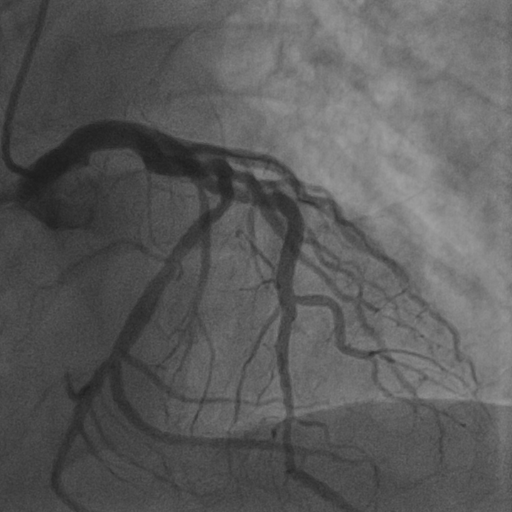

4.1 XACV Dataset